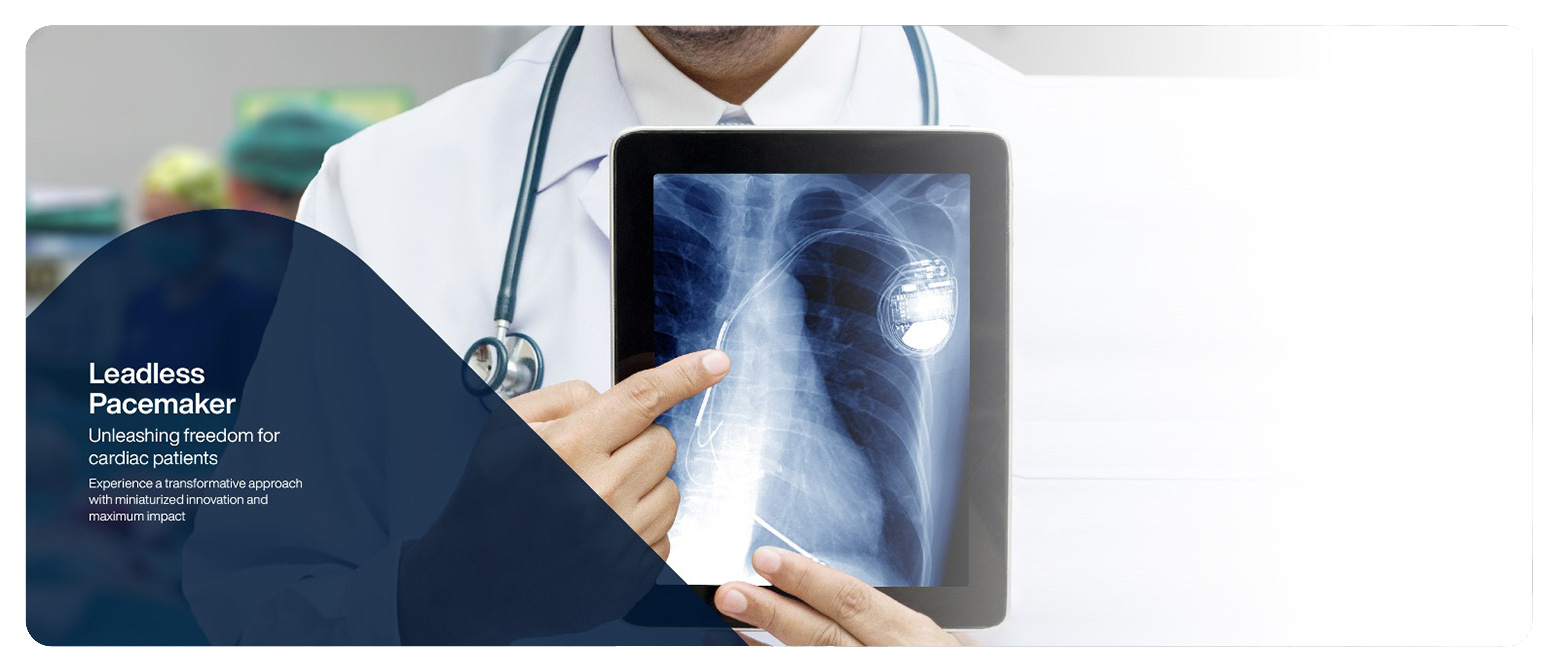

With heart disease becoming quite common nowadays, we at Eternal Hospital, are seamlessly involved in curating the finest treatments to curb the same with the use of world-class technology and the most advanced modalities like Pacemakers, Implantable Cardioverter Defibrillators and Cardiac Resynchronization Therapy. We have a dedicated team of cardiologists and cardiac surgeons holding immense specialization in pacemaker implantation. We analyse and assess every patient thoroughly, adhering to a personalized approach for your hassle-free recovery. You will be guided on every step and briefed about the procedure in detail to help you make an informed decision that yields the best outcomes for you.

A pacemaker is a medical device that helps regulate abnormal heart rhythms. It is surgically implanted in the patient’s chest. It sends electrical impulses to the heart to make it beat in a regular pattern. A pacemaker can also be referred to as a cardioverter-defibrillator (CVR). It consists of a small battery-powered generator and leads that are implanted into the heart. This generator transmits electrical impulses to the heart to maintain a consistent heartbeat. Pacemakers are commonly used to treat conditions such as bradycardia (slow heart rate) and heart block. Pacemakers offer various benefits to individuals with heart conditions, helping them to improve symptoms and reduce complications. However, a regular visit to a cardiologist is mandatory for proper evaluation and keeping track of your prognosis.

There are several types of pacemakers available, to suit the specific needs of different patients.